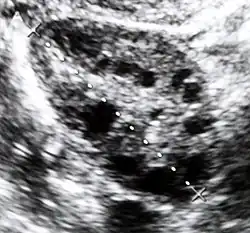

| Diagnostic method | Blood tests, ultrasound[1][4] |

Polycystic ovary syndrome accounts for about 70% of hyperandrogenism cases.[1] Other causes include Congenital adrenal hyperplasia, insulin resistance, hyperprolactinemia, Cushing's disease, certain types of cancers, and certain medications.[4][1][3] Diagnosis often involves blood tests for testosterone, 17-hydroxyprogesterone, and prolactin, as well as a pelvic ultrasound.[1][4]

Polycystic ovary syndrome (PCOS) is an endocrine disorder characterized by an excess of androgens produced by the ovaries. It is estimated that approximately 90% of women with PCOS demonstrate hypersecretion of these hormones.[19] The cause of this condition is unknown. Speculations include genetic predisposition; however, the gene or genes responsible for this remain unidentified.[20] The condition may have a hereditary basis. Other possible causes include elevated insulin production. Most cases of PCOS involve insulin resistance.[21] It is thought that adipose tissue dysfunction plays a role in the insulin resistance seen in PCOS.[21] Insulin can induce excess testosterone secretion from the ovaries.[22] A complication associated with polycystic ovary syndrome is high cholesterol, which is treated with statins. In a meta-analysis, atorvastatin was shown to decrease androgen concentrations in people with hyperandrogenism.[23]